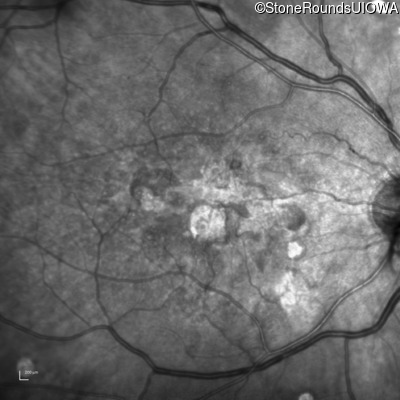

Malattia Leventinese (IIJ)

Malattia Leventinese (IIJ)

This 43 year old woman has experienced a gradual reduction in her central vision for the past 3 years.

| Malattia Leventinese | EFEMP1 | Arg345Trp CGG>TGG | AD |